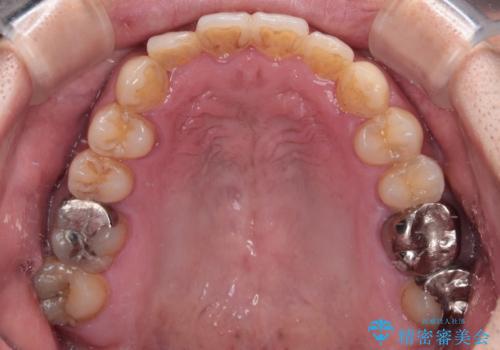

- 前歯のデコボコを気にして来院された患者様です。

前歯が90度近く捻れていたため、しっかりと治すことを考えるとワイヤー矯正の方がおすすめではありましたが、本人の希望によりインビザラインを用いて矯正治療を行うこととしました。

インビザラインは、十分な装着時間が達成されると前歯のデコボコをしっかりと改善できますが、1日の装着時間が20時間に達しなくなると、不十分な仕上がりとなるため、しっかりと装着するよう指示をしました。

途中2年強の来院がなく、改善されていたデコボコが元に戻ったり、装着時間が不足しており前歯のデコボコは十分に改善することはできませんでしたが、5年間の有効期限内で可能な限り歯列を整えることができました。